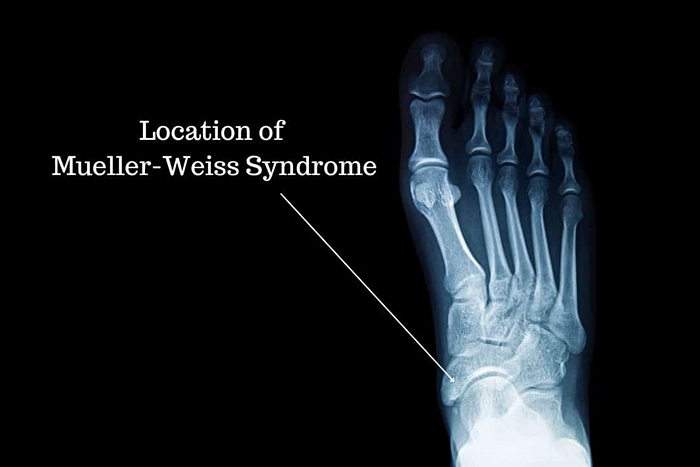

나달은 열아홉 살 때 뮐러 와이스 증후군 진단을 받았습니다.

발뼈 조직에 변형을 일으키는 이 유전병으로 나달은 고질적인 통증을 안고 대회를 치러야 했습니다.